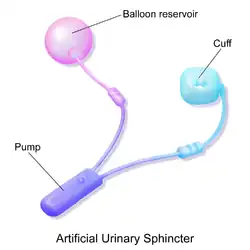

Existem dois tipos de esfíncteres urinários artificiais:

- O esfíncter urinário artificial de três componentes: manguito de controle, bomba e balão. O manguito de controle é colocado ao redor da uretra; a bomba é inserida no escroto, e o balão é implantado no espaço retropúbico - entre a bexiga e a veia ilíaca. A pressão do circuito hidráulico é gerado pelo balão a partoir do espaço retropúbico[1][2]

O fator comum entre os AUS disponíveis é a constrição mecânica através de um controle inflável preenchido com uma solução salina estéril, e implantada ao redor da uretra que mantém o lúmen uretral fechado devido à pressão produzida dentro do aparelho, e um controle externo acessível, colocado entre as duas camadas de pele do escroto (bolsa subdartos) que permite ao usuário para aliviar a constrição manualmente, e permitir a micção.